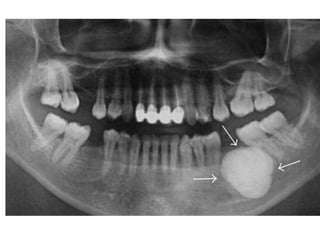

Central Osteoma anterior to remaining roots of lower 7

Peripheral osteoma located in maxillary sinus

Peripheral osteoma in right angle of the mandible

It may confused with calcified lymph noads

Osteoma

• ♂ >♀, 40 y & above

• Asymptomatic until interferes with function

• Overlying mucosa is normal and freely mobile.

• Mand. > Max. & Paranasal sinuses

frontoethmoidal

• Well-defined, RO (Compact),

Internal RL core (Cancellous)

A panoramic radiograph shows an osteoma

in the right mandibular angle region